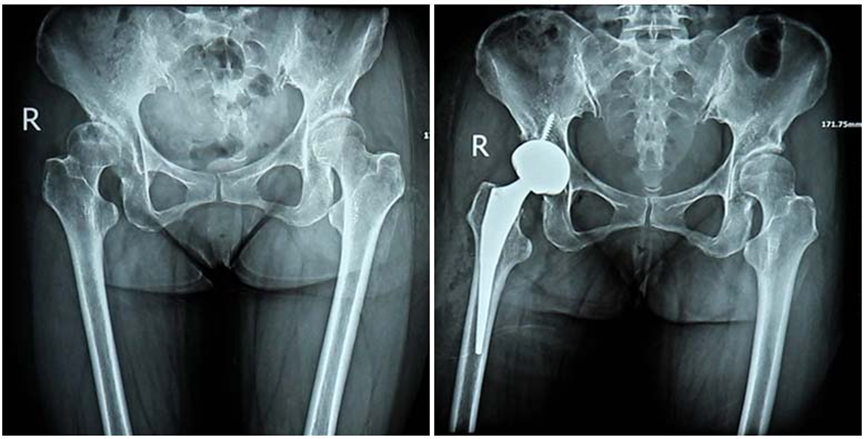

入院后,专家团队为其进行了细致的检查,发现其右侧髋臼发育浅平、股骨头覆盖不足,伴股骨头半脱位,右侧患肢较对侧缩短2公分左右。综合考虑患者的年龄、身体情况以及她渴望重返讲台、恢复正常活动能力的需求,医院专家团队为矫老师制定了骨科机器人辅助DAA入路全髋关节置换的手术方案。

济南关节外科医院肖国文院长介绍,相比其他入路方式,DAA入路无需切开任何肌肉、血管和神经,而是通过人体自身的肌肉间隙到达手术部位,能最大程度保护髋周软组织,降低术后脱位的风险,减少创伤,为患者快速康复奠定基础。手术中再辅助手术机器人,有效解决了先髋患者解剖结构变异大、标志点不清晰的难题,让假体植入、定位等关键手术操作更加精准。DAA入路+手术机器人的治疗方式,不仅实现了手术的精准化、微创化,其在恢复患者正常生物力学,调整肢体长度,延长假体使用寿命,降低远期翻修的风险,改善关节功能等方面具有显著的优势。